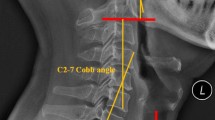

When the type of foraminal stenosis was divided into two areas, at the entrance to the canal and within the foraminal canal10, we found that the additional images were particularly useful when the foraminal stenosis was not located at the entrance to the canal (Fig. 1a,b) but located within the foraminal canal (Fig. 2a,b). In fact, of a total of 24 decompressed foramina, 23 were within the foraminal canal and only one foramen was at the entrance to the canal.

(a) Axial CT at C5/6: Line is a sagittal slice direction; arrow is an osteophyte direction. (b) Left: Foraminal narrowing at C5/6 in normal sagittal CT; Right: Foraminal narrowing at C5/6 in oblique reformatted sagittal CT. Both were observed in the same patient, but the normal sagittal view showed less foraminal narrowing.

There are a number of reasons for why foraminal narrowing is better appreciated on oblique sagittal CT and 3DCT images. First, in the stenosis area at the entrance to the canal, the osteophyte projects directly posteriorly in the same plane as the sagittal slice. Therefore, there is minimal advantage to the additional images (Fig. 1). In contrast, foraminal narrowing due to intraforaminal osteophytes was better appreciated on the oblique sagittal images. This is because the foraminal canal is oriented in an oblique angle. Therefore, an oblique sagittal image is required to see the foramen in perfect cross section. If we consider foramen as a cylinder, oblique sagittal images cut perpendicular to the cylinder such that each image is perfectly circular. However, standard sagittal images cut oblique to the cylinder such that each image is oval (Fig. 3). Therefore, the foramen space was observed as enlarged and emphasized in standard sagittal images owing to the fact that an oval is larger than a circle (Fig. 2).